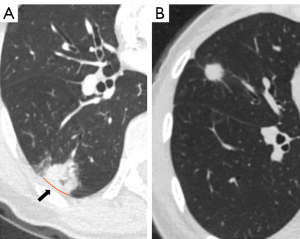

Chest CT scans were performed for all patients included in the study within 1 month prior to surgery, using Siemens Somatom Definition AS scanners (Siemens Medical Systems, Erlangen, Germany) or Philips Brilliance 40 scanners (Philips Healthcare, Cleveland, USA). CT parameters were 120 kVp tube voltage, 200 mAs tube current, pitch of 0.875–1.5, and detector collimation of 1–2.5. Images were reconstructed at 1.0-mm intervals and independently reviewed by 2 experienced thoracic radiologists. Disagreements were resolved through discussions with a third radiologist with more than 20 years of clinical experience in thoracic imaging. CT characteristics were examined in both the lung (window width 1,500 HU and level 600 HU) and mediastinal (window width 350 HU and level 50 HU) window settings. Records of radiographic parameters, including tumor size and location, nodule type, and solid portion size, were obtained for each patient. For tumors with pleural involvement confirmed three-dimensionally on CT images, tumor-pleura relationships were classified as pleural contact (abutting the pleural surface) or pleural tag (Figure 1). A pleural tag was characterized as one or more linear soft tissue strands, appearing as continuous linear opacities on CT scans, extending from the tumor surface to contact perpendicularly with the pleural surface. These tags were likely the result of the thickening of the interlobular septa of the lung, possibly due to pathological processes associated with tumor development, including fibrosis (28-30). The interface solid portion (ISP) length was measured as the solid portion length of tumor-pleura interface. The proportion of the length of the involved interface was calculated as: (tumor-pleura interface length)/(maximum tumor diameter) ×100%. Minimum distances between nodules and pleura were measured in nodules with a pleural tag.